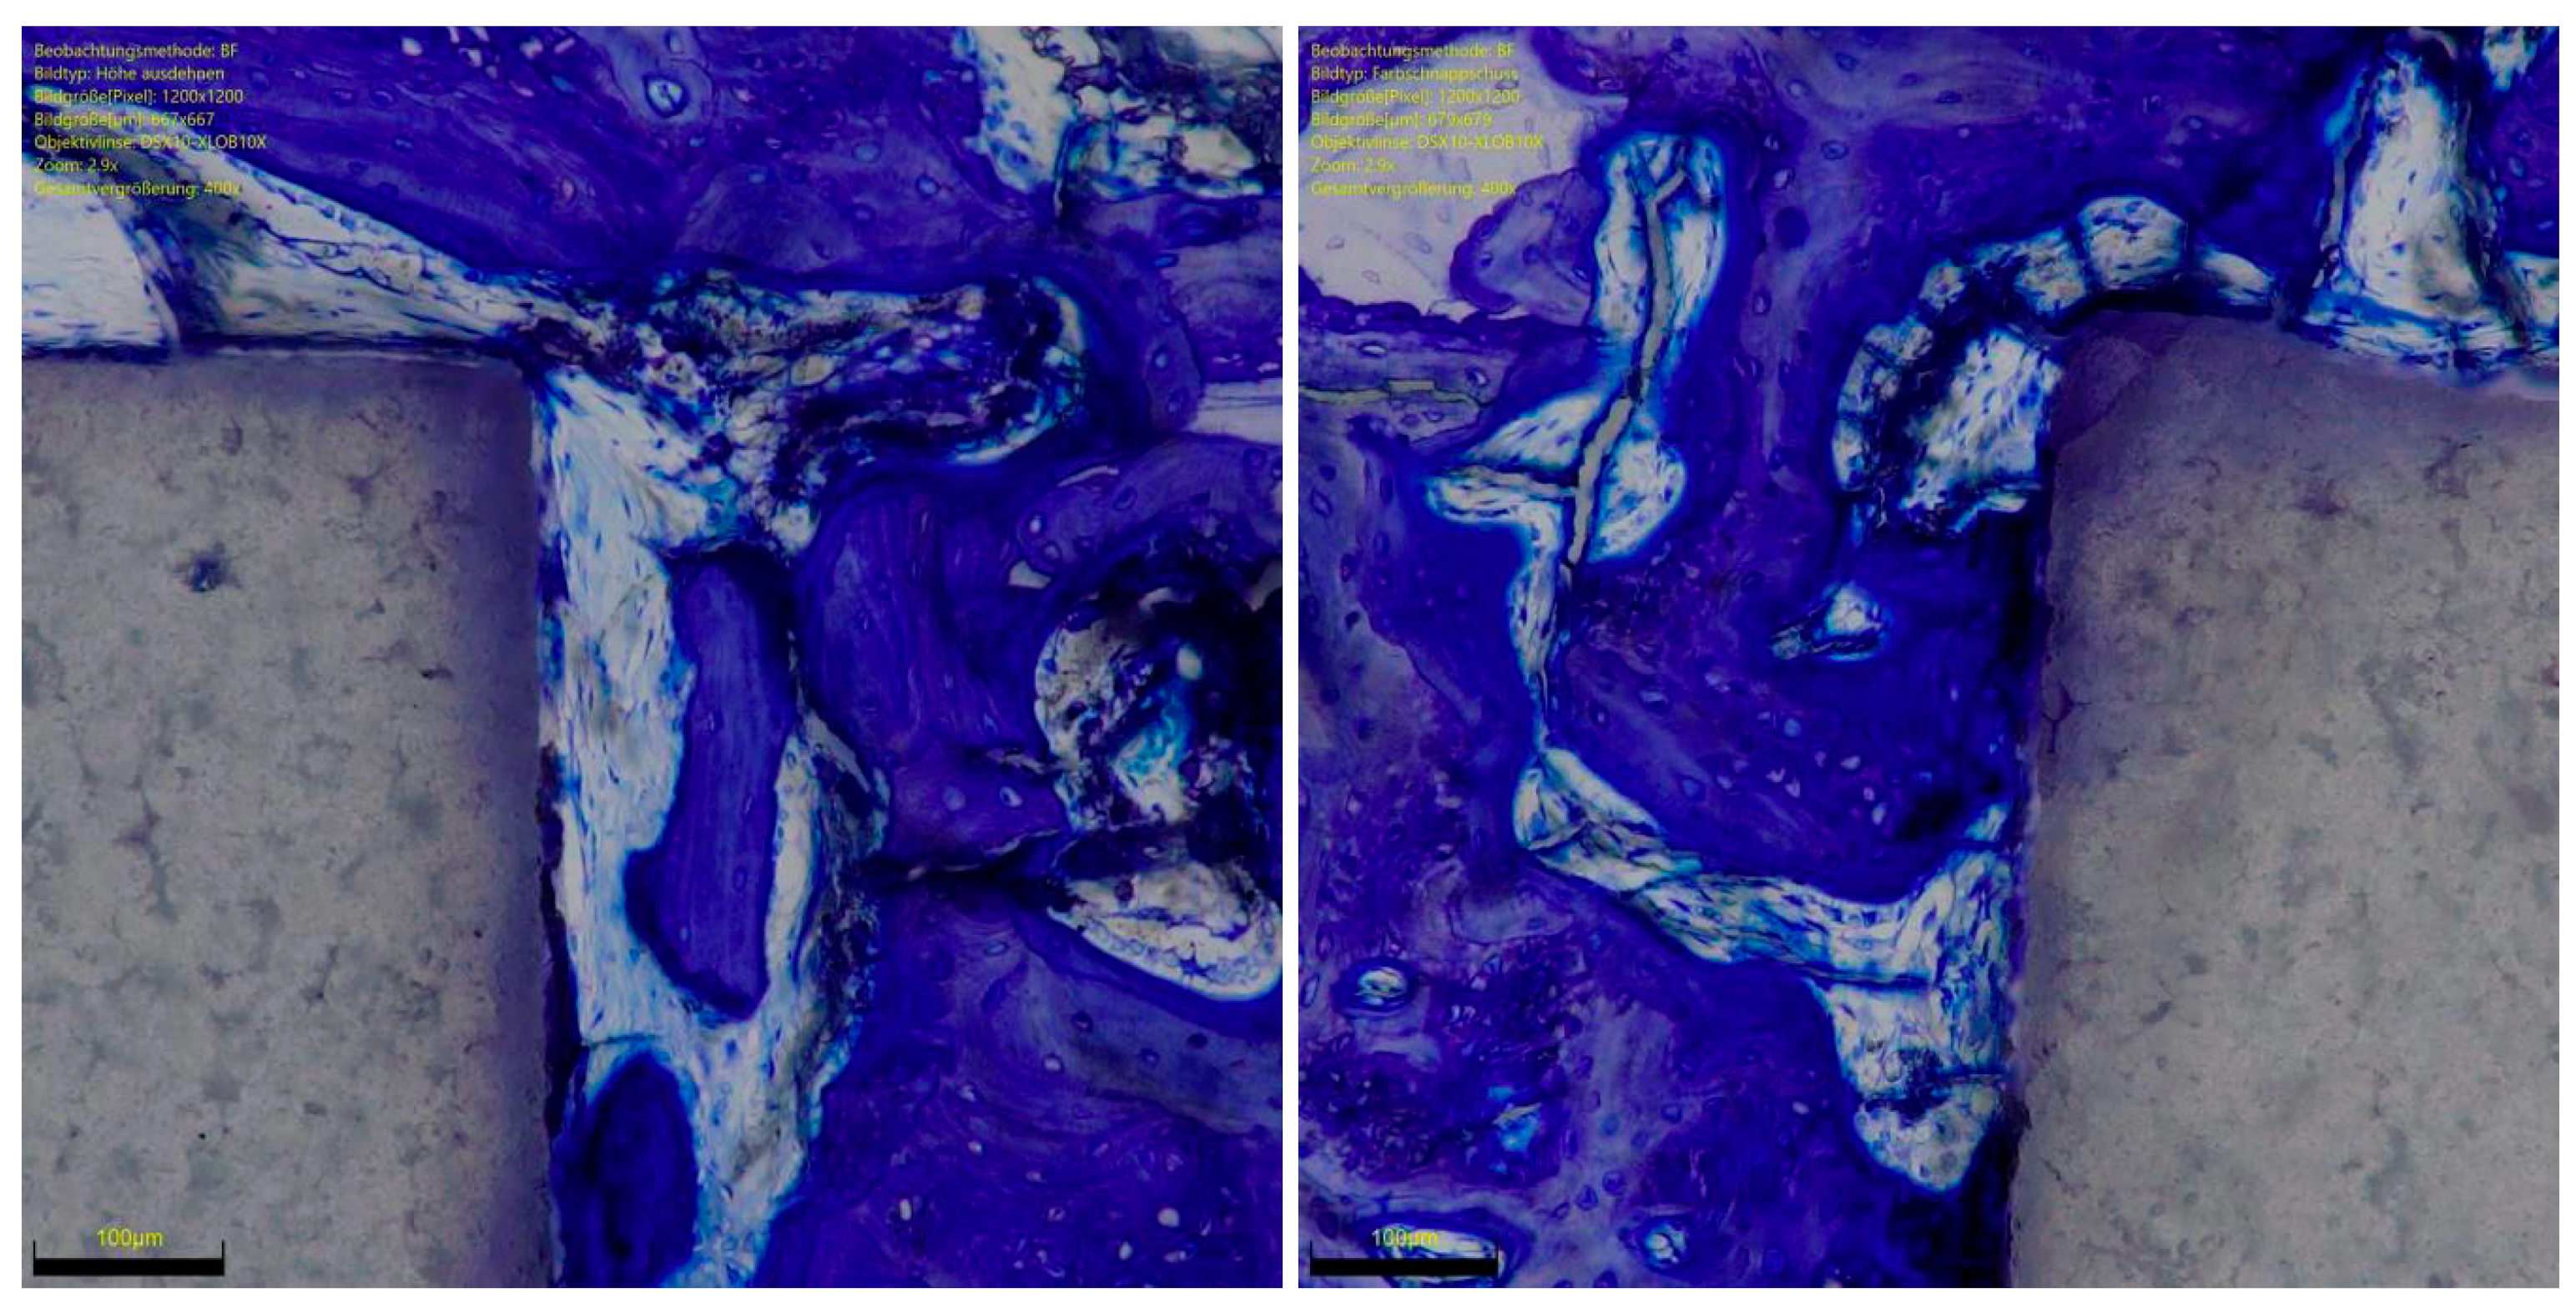

Ceramic implants have several advantages, such as their high hardness and wear resistance, light weight, low modulus of elasticity, outstanding resistance to creep and compressive stress, and no artefacts at imaging [10,11,12]. Functionalised ceramics with RGD biologically activate the implant surface, enhancing the interaction at the bone implant interface, thus preserving the overall structure and characteristics of the ceramic. The present study confirmed our hypothesis that functionalised ceramic implants enhanced with peptide RGD promote in vivo ossification (Figure 5 and Figure 6). The overall osteoid and bone implant contact improved significantly from 6 to 12 weeks. Finally, RGD enhanced ceramics promoted faster osteoid implant contact in vivo than titanium implants. Overall, the amount of ossification at 12 weeks is comparable between the two implants. No necrosis, bone resorption, or inflammation was observed in any sample at any follow-up.

Figure 6. Left: Titanium implant in polarised light toluidine blue staining with adjacent newly formed bone, polarised optically magenta-orange and local bone blue. Right: RGD functionalised ceramic implant in trichrome staining with adjacent new bone formation in red-green and local bone in green.